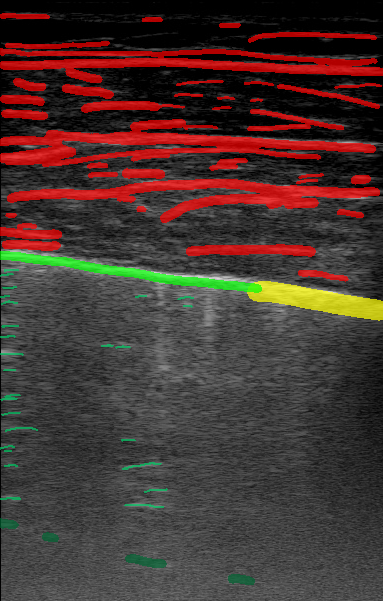

Figure 1 is an example segmentation label, thresholded by confidence to show the distribution of confidences in a single example. As the confidence threshold increases, the resulting segmentation labels get more refined. However, there may be a loss of features in the labels once the thresholds get sufficiently higher than the expert’s confidence in that feature’s appearance. For example, vertical lines disappear once the threshold becomes 40% in Figure 1. By thresholding the confidence labels this way and conducting further analysis with downstream tasks, we can gain a sense of how prominent these LUS features need to be for them to be clinically relevant.

| LUS Image | Soft Label | |||||||

|---|---|---|---|---|---|---|---|---|